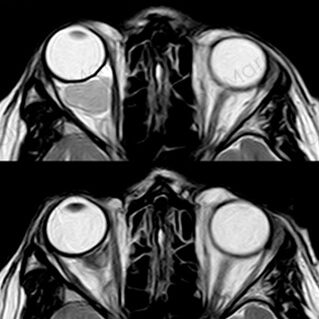

ORBITOPATÍA TIROIDEA